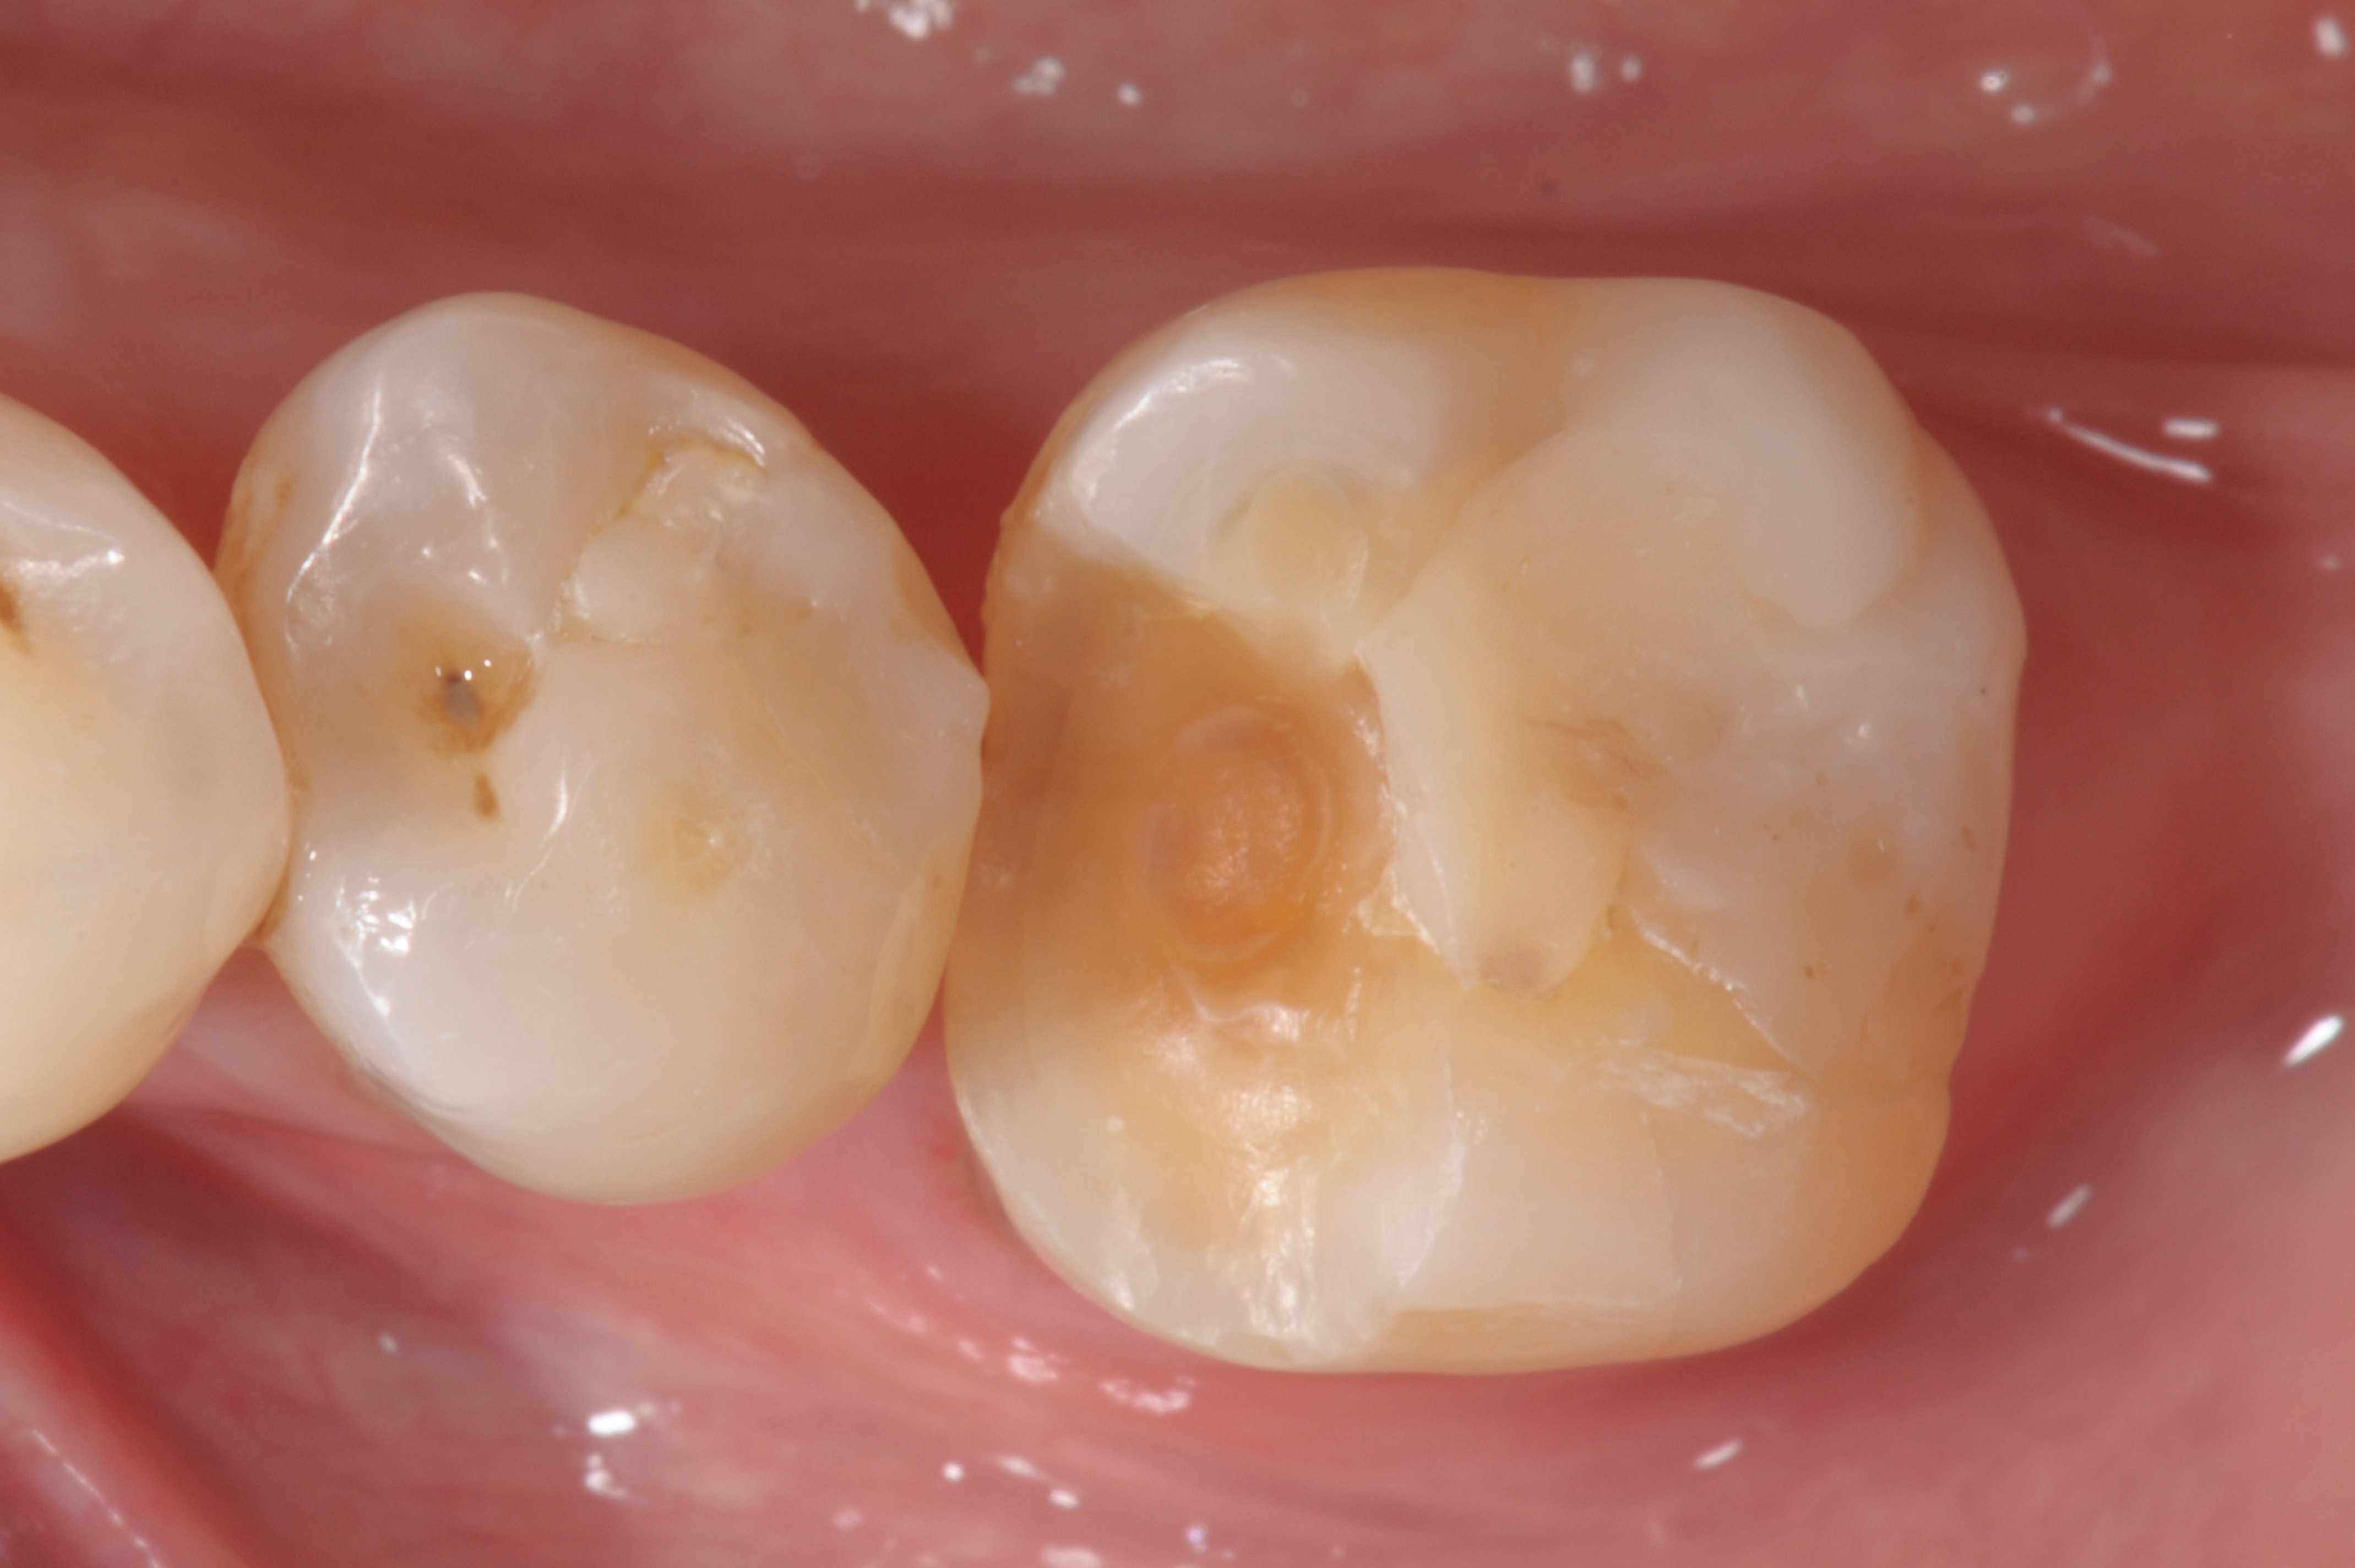

When following a protocol of cementation using an adhesive system, constant rubber dam isolation and careful hand finishing are necessary to provide predictable clinical results (Figure 1 through Figure 4).2

Fig 1. A mandibular first molar, with a fractured composite restoration: cavity preparation.

Figure 1